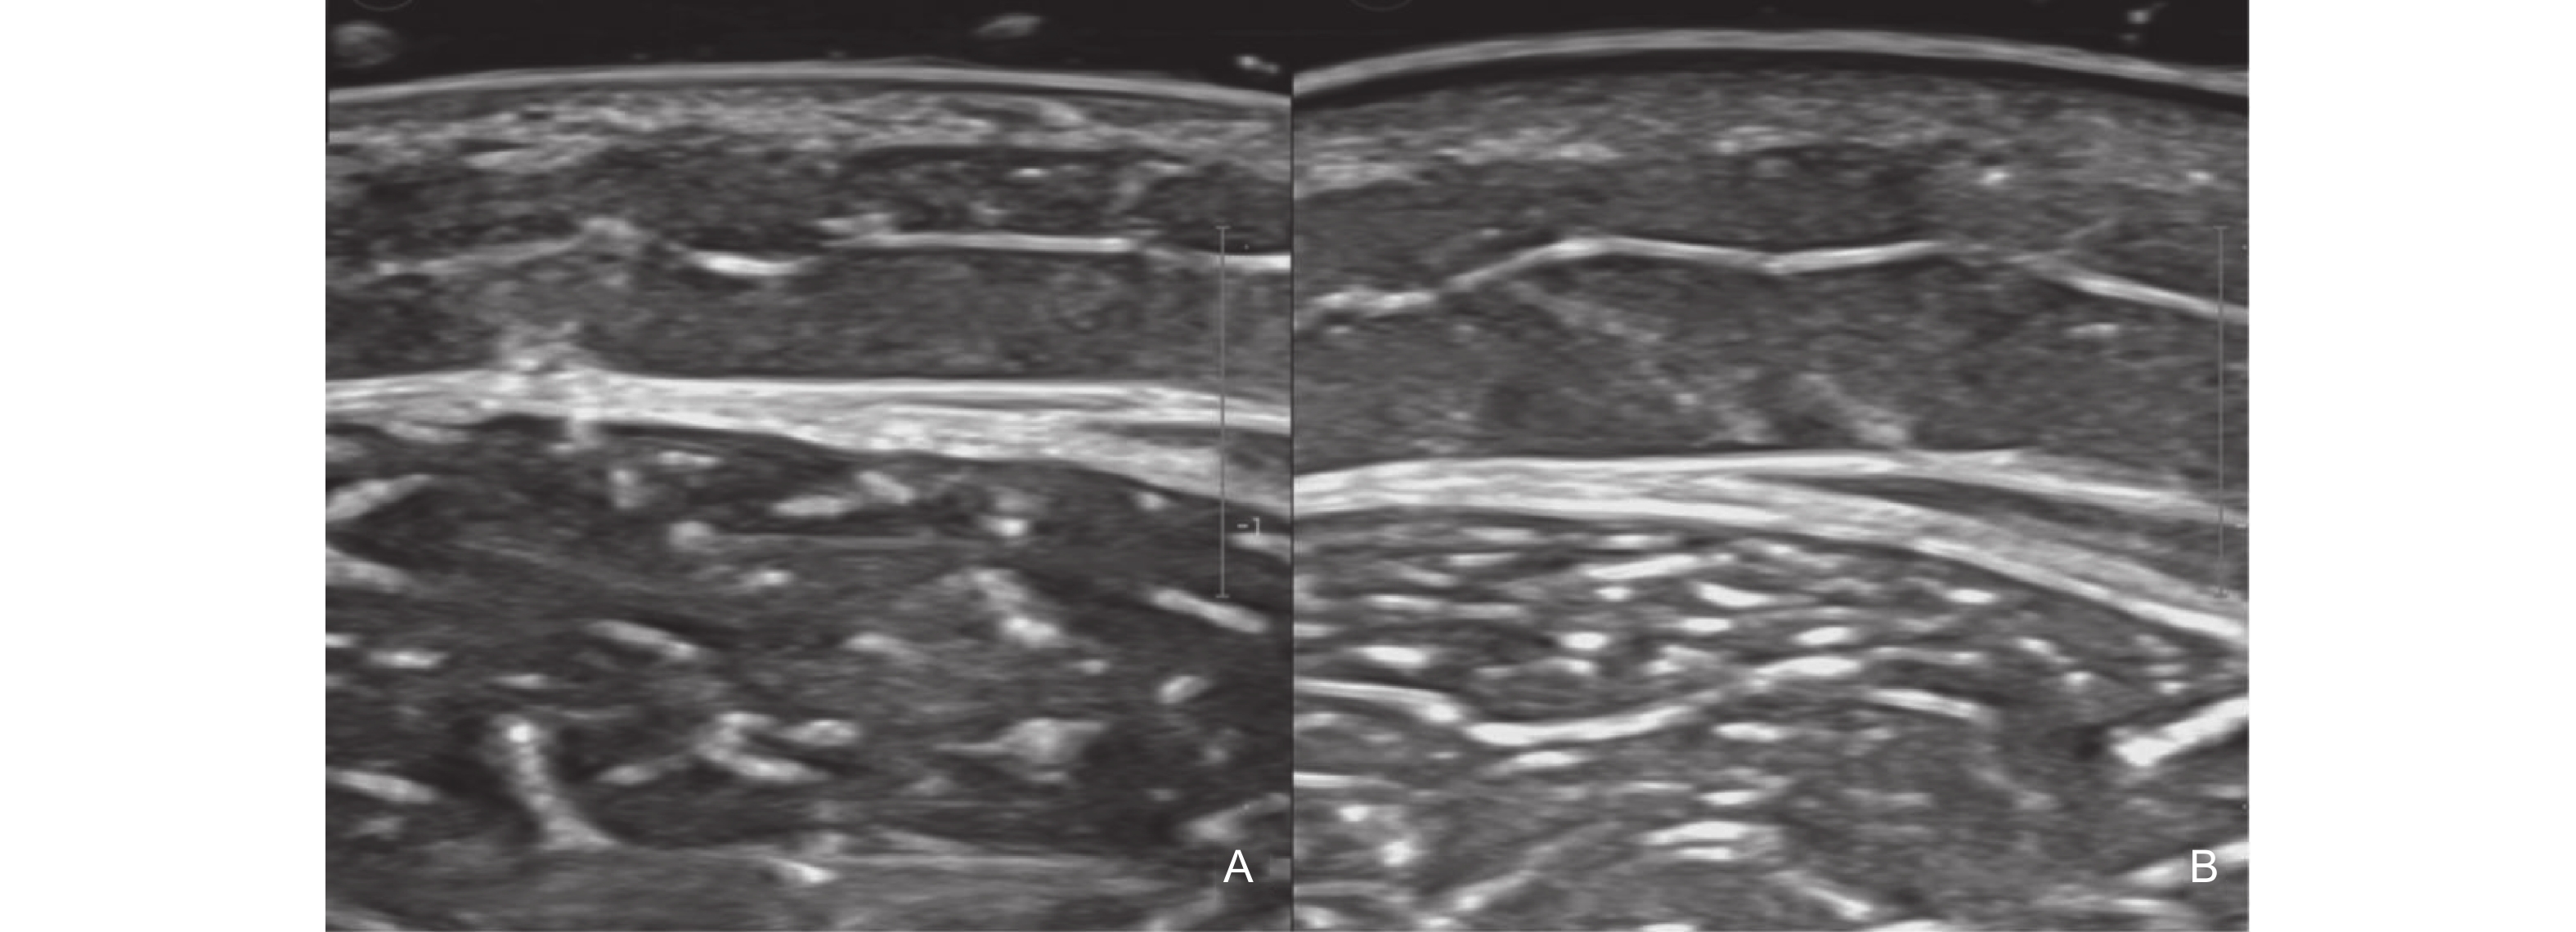

Figure 3

Clinical [47] and ultrasound manifestations of port-wine stains. (A) Pink type of PWS; (B) Purple type of PWS; (C) Thickening type of PWS; (D) Comparison of gray-scale ultrasound between the PWS lesion and the healthy side; (E) The blood flow signal at the lesion site of PWS increases."

| [47] | Xiang Xi , Zhang Lingyan , Zhong Lin , Gao Yi , Qiu Li . Multimodal ultrasound manifestations of port-wine stains and their application in efficacy assessment of photodynamic therapy. Chinese Journal of Dermatology 2024; 57: 801-806 |